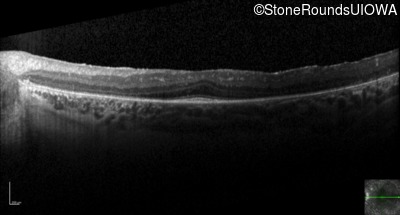

Optical Coherence Tomography - Right - 20/50

Exemplar / OCT Stack

OCT Stack